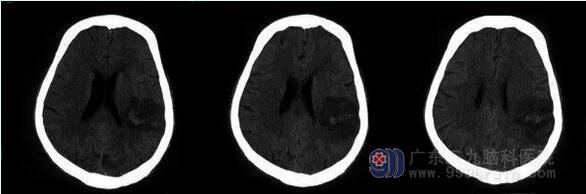

神经内一科主任王展航介绍,张伯这次发病的责任病灶位于左侧顶枕叶,从CT等影像检查结果可以判断,张伯是出血性脑梗死。“相比较一般的出血性脑梗死,张伯的情况还有些特殊,是比较少见的甲状腺功能亢进合并脑血管出血。”